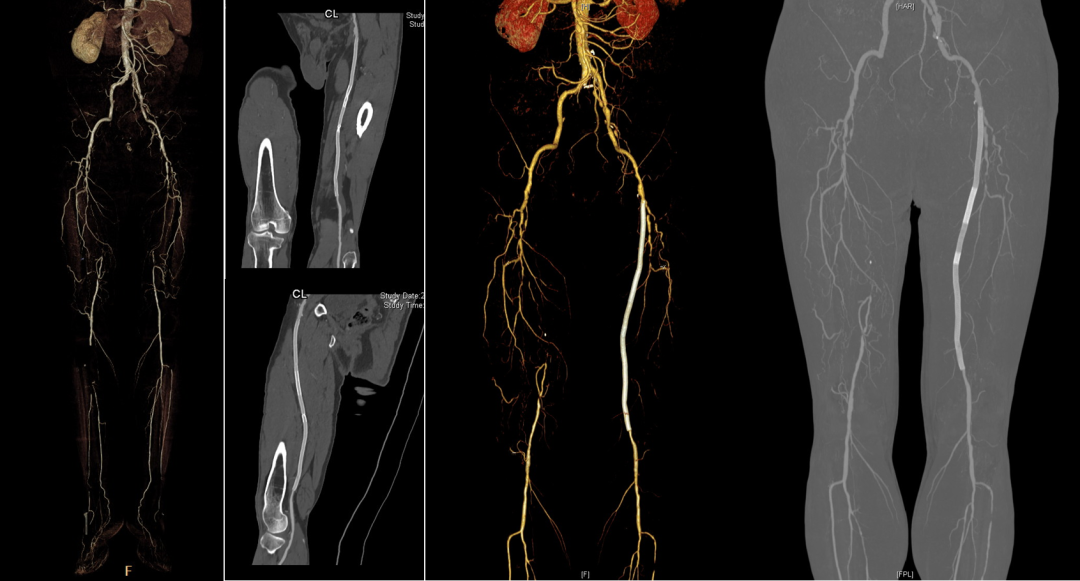

★ Case 5

Female,82 y

Severe claudication over 1 year in both extremities esp. in the left

DM over 10 years

CTA:SFA-PA long CTO

左右滑动查看